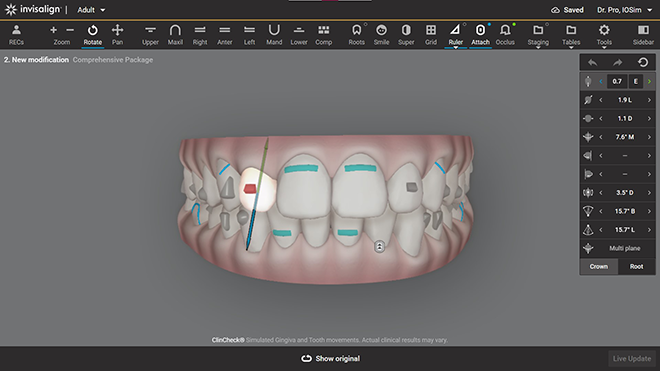

2. CLINCHECK 3D – MÔ PHỎNG TOÀN BỘ HÀNH TRÌNH TRƯỚC KHI BẮT ĐẦU

2.1. Nhìn thấy kết quả trước khi điều trị

Một trong những điểm khác biệt lớn của Invisalign là hệ thống ClinCheck 3D. Đây là phần mềm cho phép mô phỏng toàn bộ quá trình dịch chuyển răng từ thời điểm bắt đầu đến khi kết thúc.

2.2. Không phải “đeo rồi xem sao”

Trong chỉnh nha, yếu tố dự đoán rất quan trọng. Với ClinCheck, mỗi bước dịch chuyển đều được tính toán trước, thay vì điều chỉnh liên tục trong quá trình như một số phương pháp khác.

Tại Bệnh viện RHM Worldwide, kế hoạch ClinCheck được phân tích kỹ lưỡng bởi bác sĩ trước khi sản xuất khay, đảm bảo lực di chuyển phù hợp với từng cấu trúc xương và khớp cắn cụ thể.

4. ATTACHMENTS – KIỂM SOÁT LỰC DI CHUYỂN CHÍNH XÁC

Khi điều trị bằng Invisalign, bác sĩ có thể gắn các điểm tựa nhỏ gọi là attachments lên răng. Những điểm này giúp:

Attachments không được đặt ngẫu nhiên. Chúng được tính toán dựa trên mô phỏng ClinCheck và mục tiêu điều trị cụ thể.

Công nghệ ClinCheck cho phép xây dựng kế hoạch điều trị cá nhân hóa, giúp tối ưu hiệu quả chỉnh nha cho từng trường hợp.